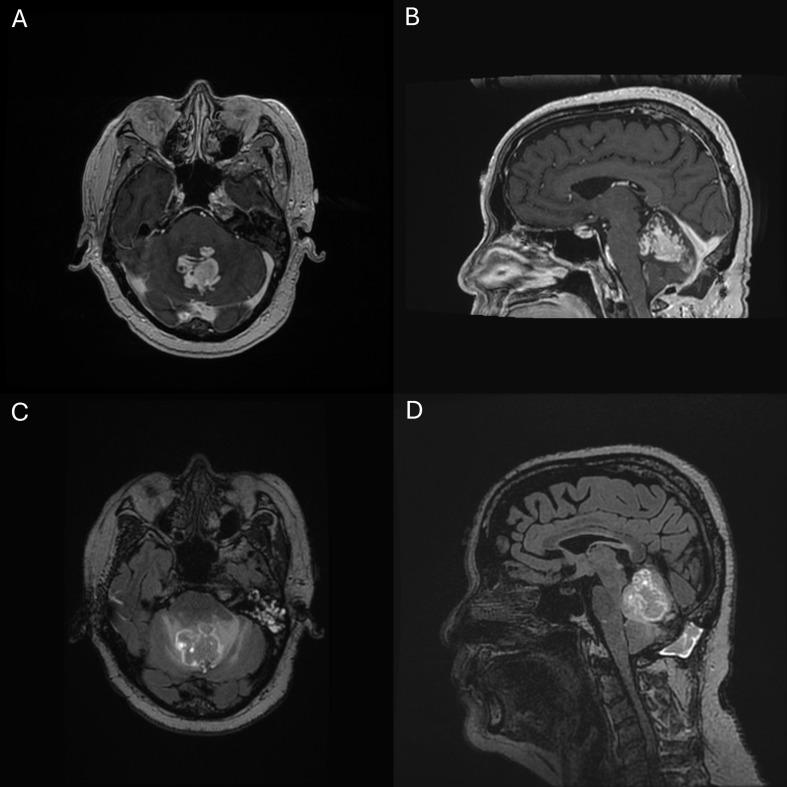

High-grade astrocytoma with piloid features (HGAP) is a recently described primary brain tumor and the first requiring a specific methylation pattern for diagnosis, as its histologic features are often compatible with other tumors such as glioblastoma (GBM). Characterized by molecular alterations in CDKN2A/B, NF1, BRAF, FGFR1, and ATRX, they may be located anywhere in the CNS but show a predilection for the posterior fossa. Reports are limited to retrospective case series, and the standard of care is not yet established. We performed a retrospective review of electronic medical records of all patients with HGAP at our institution. Records were queried for demographic, radiographic, clinical, surgical, pathologic, and outcome data. Eighteen patients were included with a median 17.1 months follow-up. Of these, 12 (63.2%) were women with a mean age of 43 years (range 24-67). The most common tumor locations were the cerebellum (8 patients, 42.1%) and thalamus (6 patients, 31.6%). On imaging, tumors were most commonly homogeneously contrast-enhancing (10 patients, 52.6%) or rim enhancing with central necrosis (5 patients, 26.3%). Ten patients (52.6%) underwent biopsy, while nine (47.4%) underwent resection, of which four (44.4%) underwent gross total resection. Adjuvant therapy included radiation in 16 patients (88.9%) and systemic treatment in 16 patients (88.9%). The initial systemic treatment was temozolomide in 14 patients (77.8%). One patient received upfront trametinib (a MEK1 inhibitor), and one patient received upfront dabrafenib (a BRAF inhibitor). At last follow up, 11 patients (57.9%) had progressive disease. Median progression-free survival (PFS) was 5.4 months (range 1.6-28.2 months), and median overall survival (OS) had not been reached. HGAP is a newly described rare glial tumor without an established standard of care. Its aggressive behavior and targetable mutations warrant further investigation regarding predictors of outcome for this entity.

具有毛细胞样特征的高级别星形细胞瘤(HGAP)是一种最近被描述的原发性脑肿瘤,也是第一种诊断需要特定甲基化模式的肿瘤,因为其组织学特征常与其他肿瘤如胶质母细胞瘤(GBM)相符。其特征为CDKN2A/B、NF1、BRAF、FGFR1和ATRX的分子改变,可位于中枢神经系统的任何部位,但好发于后颅窝。相关报道仅限于回顾性病例系列,且尚未确立标准治疗方案。我们对本机构所有HGAP患者的电子病历进行了回顾性分析。查询记录以获取人口统计学、影像学、临床、手术、病理及预后数据。共纳入18例患者,中位随访时间为17.1个月。其中,12例(63.2%)为女性,平均年龄43岁(范围24 - 67岁)。最常见的肿瘤部位是小脑(8例,42.1%)和丘脑(6例,31.6%)。影像学上,肿瘤最常见的表现为均匀强化(10例,52.6%)或环状强化伴中央坏死(5例,26.3%)。10例患者(52.6%)接受了活检,9例(47.4%)接受了切除术,其中4例(44.4%)进行了全切。辅助治疗包括16例患者(88.9%)接受了放疗,16例患者(88.9%)接受了全身治疗。初始全身治疗中,14例患者(77.8%)使用了替莫唑胺。1例患者接受了一线曲美替尼(一种MEK1抑制剂)治疗,1例患者接受了一线达拉非尼(一种BRAF抑制剂)治疗。在最后一次随访时,11例患者(57.9%)出现疾病进展。中位无进展生存期(PFS)为5.4个月(范围1.6 - 28.2个月),中位总生存期(OS)尚未达到。HGAP是一种新描述的罕见胶质肿瘤,尚无既定的标准治疗方案。其侵袭性行为和可靶向的突变值得对该实体的预后预测因素进行进一步研究。